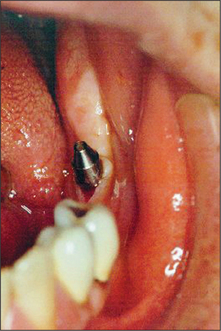

Second-stage surgery to expose an implant

After the healing phase is complete it can sometimes be difficult to determine the exact location of a two-stage (submucosal) implant. A dental probe can be used to palpate the cover screw through the anaesthetized tissues. Once the cover screw is located, a crestal incision is made to expose it (Fig. 11.30). The cover screw is then removed and a healing abutment inserted. If necessary, resorbable sutures are placed to ensure close apposition of the oral mucosa to the healing abutment (Fig. 11.31). After a period of 7–10 days, the healing abutment is replaced with a suitable abutment that will subsequently be loaded.

image

Fig. 11.30 Second-stage surgery. The cover screw is exposed via a small incision.